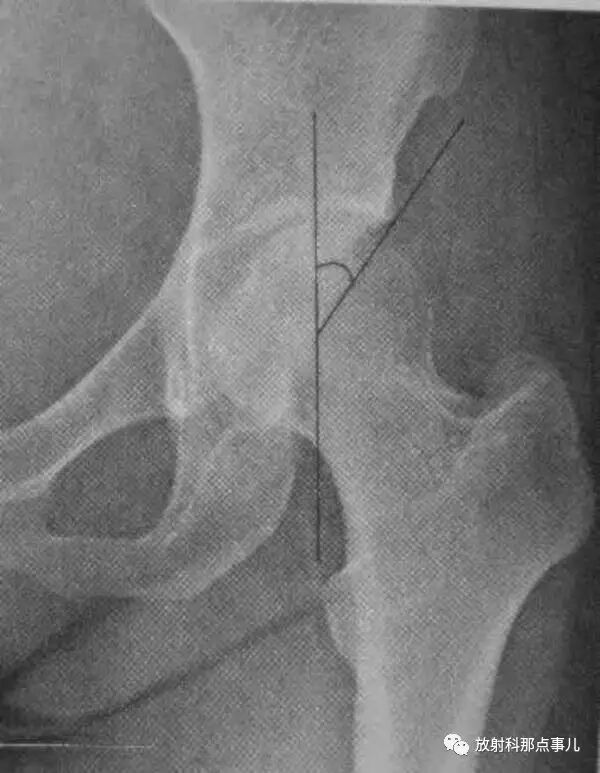

Power角

在骨盆正位片上,通过两侧髂前上棘作一水平线,然后再划股骨颈骨折线的延长线,两线相交所成的夹角。此角小于30° 者,为外展型骨折,骨折易愈合;大于30° ~90° 者,为内收型骨折,需手术纠正。

Linton角

在髋关节正位片上,先划股骨干纵轴线垂线,再划股骨颈骨折线的延长线,两线相交所成的夹角。此角小于30° 者,为外展型骨折,骨折易愈合;大于30° ~90° 者,为内收型骨折,需手术纠正。